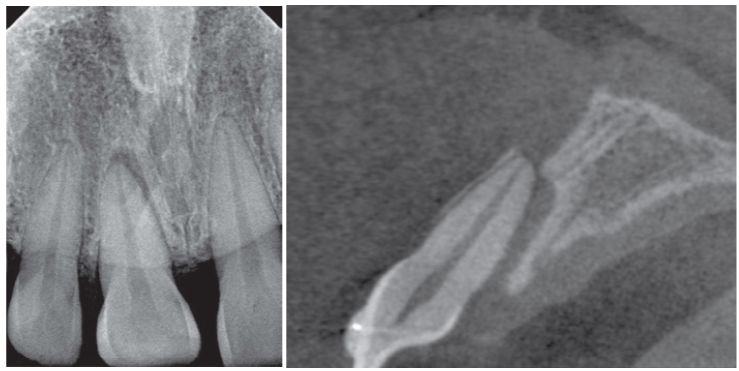

7.患者因正中門齒外傷來院就診,根尖放射片及錐狀射束電腦斷層掃描(cone-beam computed tomography, CBCT)檢查,最可能的診斷為何? (A)側向脫位(lateral luxation) (B)突出脫位(extrusive luxation) (C)半脫位(subluxation) (D)震盪(concussion)